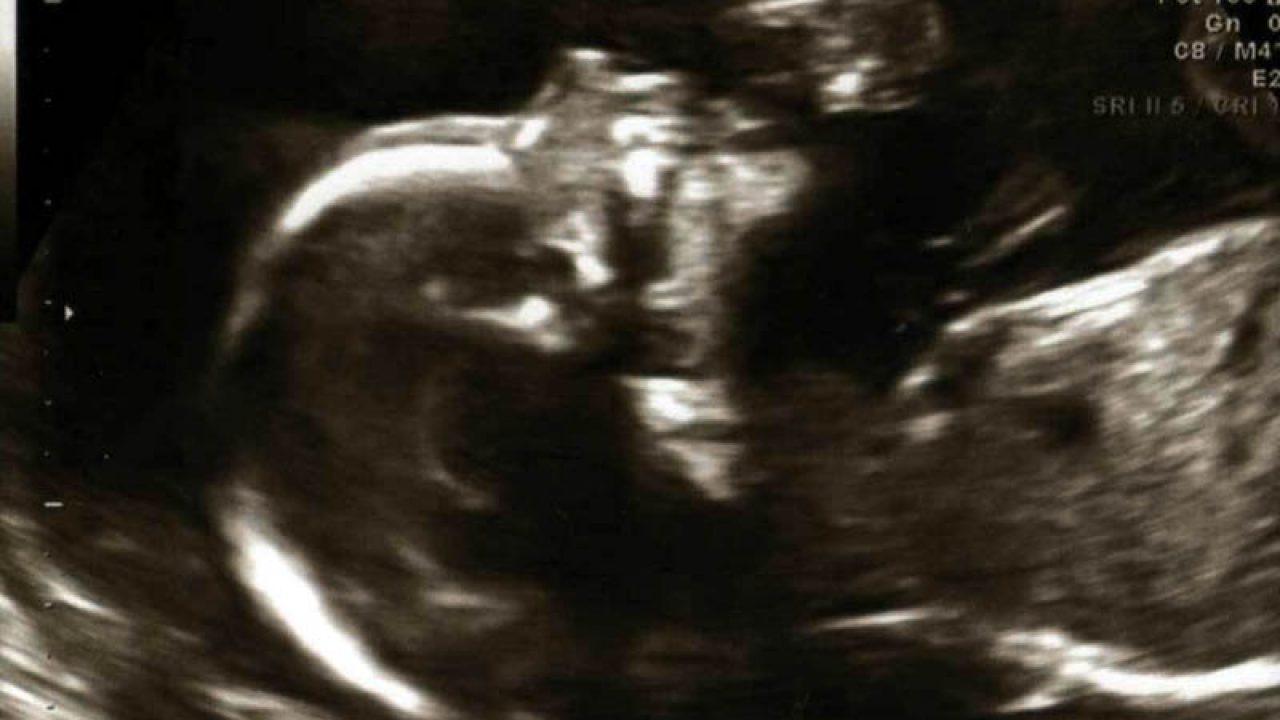

Solitamente quando si dispone di un. Quanto costa e a quante settimane si fa. Lecografia classica e bidimensionale cioe in 2d ed e in termini di accuratezza il metodo principe per la diagnosi di problematiche fetali. Iryna prokofieva shutterstock.

Se viene effettuata presso studi privati il prezzo oscilla tra i 60 e gli 80 euro. Lecografia 3d in gravidanza consente una visione tridimensionale del feto. O preco da ecografia 3d 4d a titulo particular e fixado pela clinica que a realiza. Le ecografie 3d e 4d hanno valore solo nel momento in cui si vogliano approfondire particolari sospetti evidenziati con la 2d.

Lecografia 3d in gravidanza consente una visione tridimensionale del feto. Quanto costa e a quante settimane si fa.